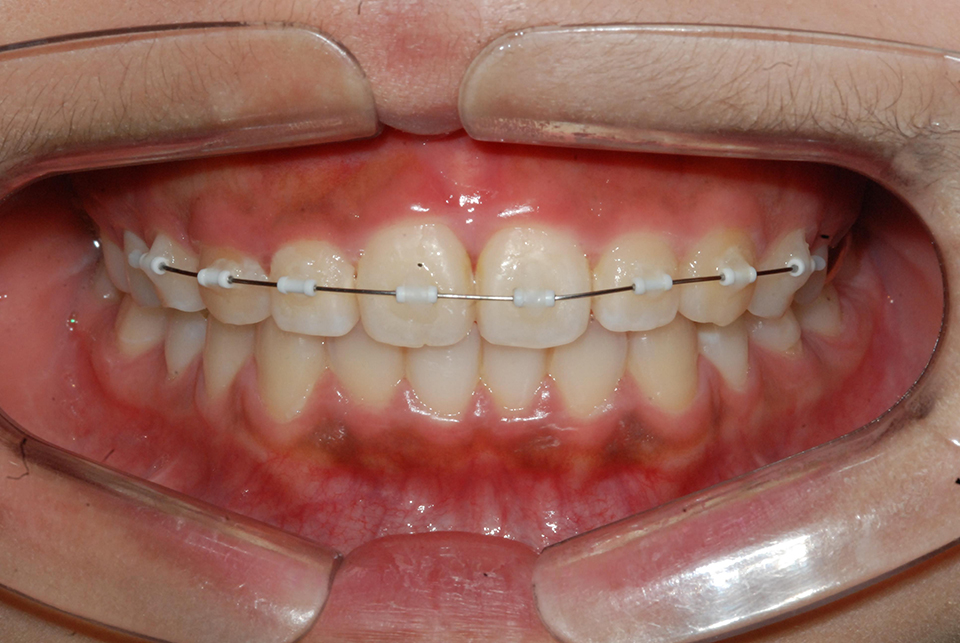

ºÎÁ¤±³ÇÕÀÌ Æ¯Á¤ ºÎÀ§¿¡ ±¹ÇѵǾî ÀÖ´Â °æ¿ì ƯÁ¤ Ä¡¾Æ¿¡¸¸ ÀåÄ¡¸¦ ºÎÂøÇÏ¿© ±³Á¤ ÇÏ´Â °æ¿ìµµ ÀÖ½À´Ï´Ù. Ʋ¾îÁ®ÀÖ´Â ¾Õ´Ï¸¸ ºÎºÐÀûÀ¸·Î °í¸£°Ô ¹è¿Çϰųª(±×¸²3) º¸Ã¶(ÀÓÇöõÆ®)À» À§ÇØ ¾²·¯Áø ¾î±Ý´Ï¸¦ ¹Ù·Î ¼¼¿ì´Â °æ¿ì(±×¸²4), »ó½ÇµÈ ´ëÇÕÄ¡ ¶§¹®¿¡ Á¤ÃâµÈ ¾î±Ý´Ï¸¦ ¾ÐÇϽÃŰ´Â Ä¡·á°¡ ´ëÇ¥ÀûÀÎ °æ¿ìÀÔ´Ï´Ù(±×¸²5). Áõ·ÊÀÇ ³À̵µ³ª ¹è¿»óÅ¿¡ µû¶ó Åë»ó 6°³¿ù ³»¿ÜÀÇ ±â°£ÀÌ ÇÊ¿äÇÕ´Ï´Ù.

| | ±×¸²3 |